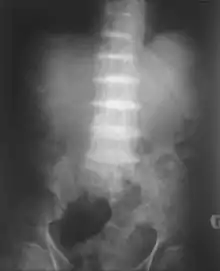

در اثر تجمع اسید هموجنتیسیک در بدن، تخریب گسترده مفاصل (بویژه در غضروفهای مهره کمر، که منجر به بروز زودهنگام کمردرد در دوران جوانی می گردد) و تشکیل سنگ در کلیهها و پروستات رخ میدهد. رسوب این ماده در دریچههای قلب (بویژه دریچه آئورت و میترال) موجب اختلالات دریچهای قلب میشود. در مراحل پیشرفته بیماری، حتی رنگ پوست و چشمها هم ممکن است برنگ قهوهای تیره مبدل شود که به این حالت در پزشکی اصطلاحاً آکرونوسیس (Ochronosis) گفته میشود و علت آن تجمع اسید هموجنتیسیک در بافت همبند است.[1] دراین بیماری به علت تجزیه نشدن اسید هموجنتیسیک، ادرار در مجاورت با هوا، سیاه رنگ میشود.